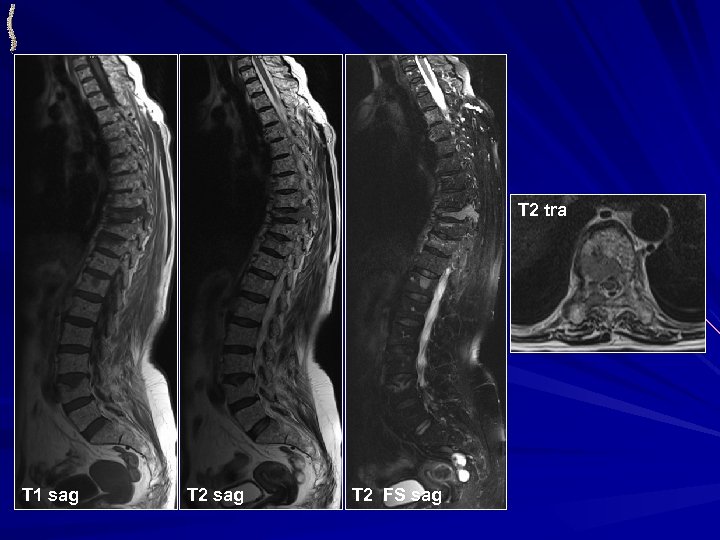

МЕТАСТАЗЫ РАКА МОЛОЧНОЙ ЖЕЛЕЗЫ • НАИБОЛЕЕ ЧАСТО ВСТРЕЧАЕМЫЕ МЕТАСТАЗЫ СОЛИДНОЙ ОПУХОЛИ У ЖЕНЩИН • НАЛИЧИЕ МЕТАСТАЗОВ В КОСТИ НЕ ЯВЛЯЕТСЯ НЕБЛАГОПРИЯТНЫМ ПРОГНОЗОМ • НАИБОЛЕЕ ЧАСТО ПОРАЖАЕТСЯ ОСЕВОЙ СКЕЛЕТ • КТ: ü Костная деструкция любого типа ü Множественность поражения • МРТ: ü Множественность поражения ü Неоднородная солидная структура очагов ü Могут быть внекостные компоненты и патологические переломы

МЕТАСТАЗЫ РАКА МОЛОЧНОЙ ЖЕЛЕЗЫ T 1 sag Th 8 T 2 sag T 2 FS sag